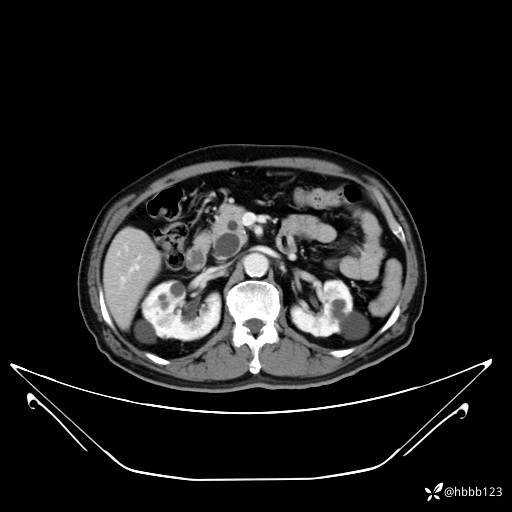

平扫: